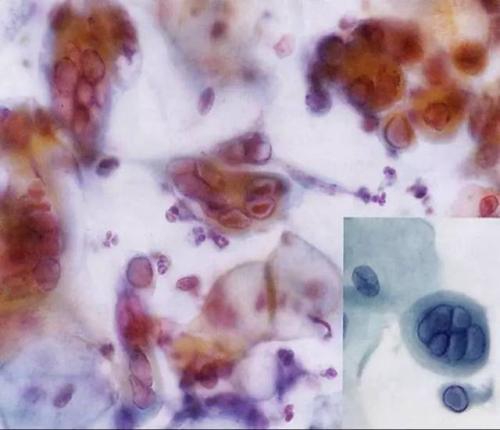

最近,1歲的萌萌(化名)頭上忽然起了一些紅疙瘩,沒過多少天,紅疙瘩竟遍布寶寶全身,讓她奇癢難忍。除螨蟲活動與挖掘隧道疥螨寄生在宿主表皮角質(zhì)層的深處,以角質(zhì)組織和淋巴液為食,并以螯肢和前跗爪挖掘,逐漸形成一條與皮膚平行的蜿蜒隧道。隧道最長可達10~15mm。以雌螨所挖的隧道最長,每隔一段距離有小縱向通道通至表皮。雄螨與后若蟲亦可單獨挖掘,但極短,前若蟲與幼蟲則不能挖掘隧道,只生活在雌螨所挖的隧道中。雌螨每天能挖0.5~5mm,一般不深入到角質(zhì)層的下面。螨蟲怎么治療螨蟲對皮膚的危害:螨蟲在皮膚里面吸取營養(yǎng)成分,刺激毛細血管以及細胞組織,引向皮膚惡化。皮膚螨蟲加速細小皺紋的產(chǎn)生,加速黃褐斑、雀斑、黑斑等色素沉著,還可導致粉刺、痘疤、痤瘡、皮膚粗糙、角質(zhì)變厚、形成凹凸皮膚。皮膚螨蟲還能形成瘙癢癥、酒糟鼻以及紅臉、紅血絲等。螨蟲怎么治療局部異物反應,引起局部炎性病變。如毛脂器官堵塞,刺激角質(zhì)層增生,毛囊擴張,毛孔粗大,毛囊營養(yǎng)不足,毛發(fā)脫落等病變。皮脂過度分泌,導致油光滿面。家人趕緊將她送到兒童醫(yī)院檢查,才發(fā)明;禍首禍首;竟是棉被里的螨蟲。專家提示,要想防螨蟲叮咬,要多開窗通風,不給螨類成長的機會;棉被在用之前要晾曬。據(jù)萌萌的母親徐女士介紹,2周前,萌萌頭上開端冒紅疙瘩,隨后頭、臉、手到處都長出了紅疙瘩。她嚇得趕緊帶著女兒到兒童醫(yī)院檢查。該院皮膚科副主任羅曉燕診斷后發(fā)明,患兒的每個紅疙瘩都有綠豆大小,晶瑩透亮,皰頂有一針尖大小的雀斑,水皰的基底部皮膚鮮紅,初步判斷寶寶患的應是丘疹性蕁麻疹,患病的起因可能是被棉被里的螨蟲叮咬所致。羅曉燕表示,螨蟲是一種肉眼看不見的小蟲子,平時愛;埋伏;在被子、枕頭、地毯、布藝沙發(fā)、草席上。每個人對螨蟲的過敏水平不同,一些對螨蟲過敏的人,受到螨蟲叮咬,就輕易過敏,并產(chǎn)生紅疙瘩。據(jù)理解,幼嬰跟兒童是螨蟲過敏癥狀極為重大的群體,他們皮膚嬌嫩,很輕易對螨蟲有過敏反應。10%的13到14歲的兒童患有塵螨過敏性鼻炎。當你家寶寶在初秋季節(jié)皮膚呈現(xiàn)皮疹,奇癢無比,甚至開端一直打噴嚏、流鼻涕,重大者哮喘發(fā)生,要警戒誤診為個別感冒咳嗽,可能恰是螨蟲沾染了!羅曉燕提示寬大家長:要想防螨蟲叮咬,首先要堅持環(huán)境的衛(wèi)生;經(jīng)常晾曬被褥;假如不太陽,可用開水淋燙,等晾干后再利用。